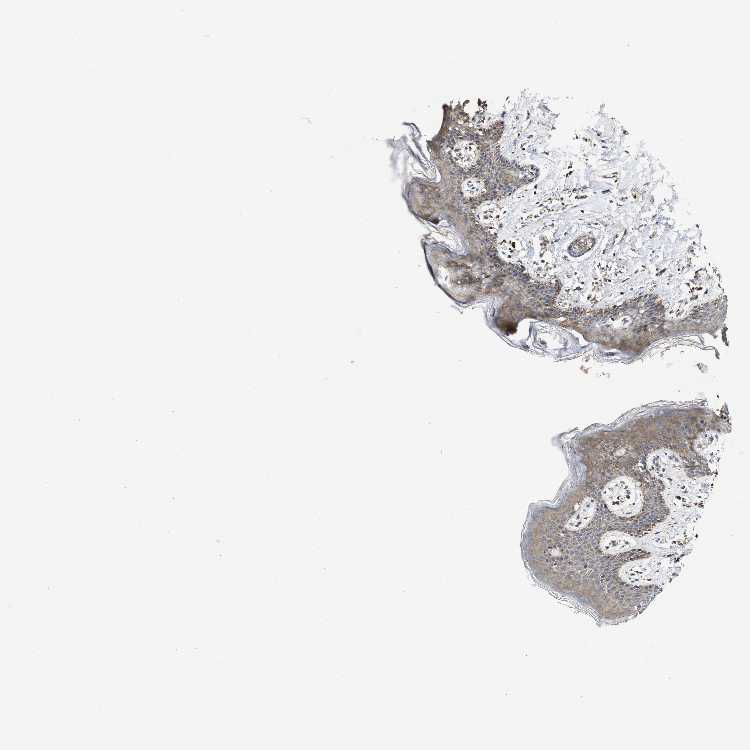

SKIN 1 - Antibody stainingi

Antibody staining in the annotated cell types in the current human tissue is reported as not detected, low, medium, or high, based on conventional immunohistochemistry profiling in selected tissues. This score is based on the combination of the staining intensity and fraction of stained cells.

Each image is clickable and will lead to virtual microscopy that enables deeper exploration of all samples and also displays staining intensity scores, fraction scores and subcellular localization as well as patient and tissue information for each sample.

Antibody HPA019805Antibody HPA020599Antibody CAB004605

Langerhans MediumNot detectedNot detected

Fibroblasts Not detectedLowMedium

Keratinocytes MediumMediumMedium

Melanocytes LowMediumMedium